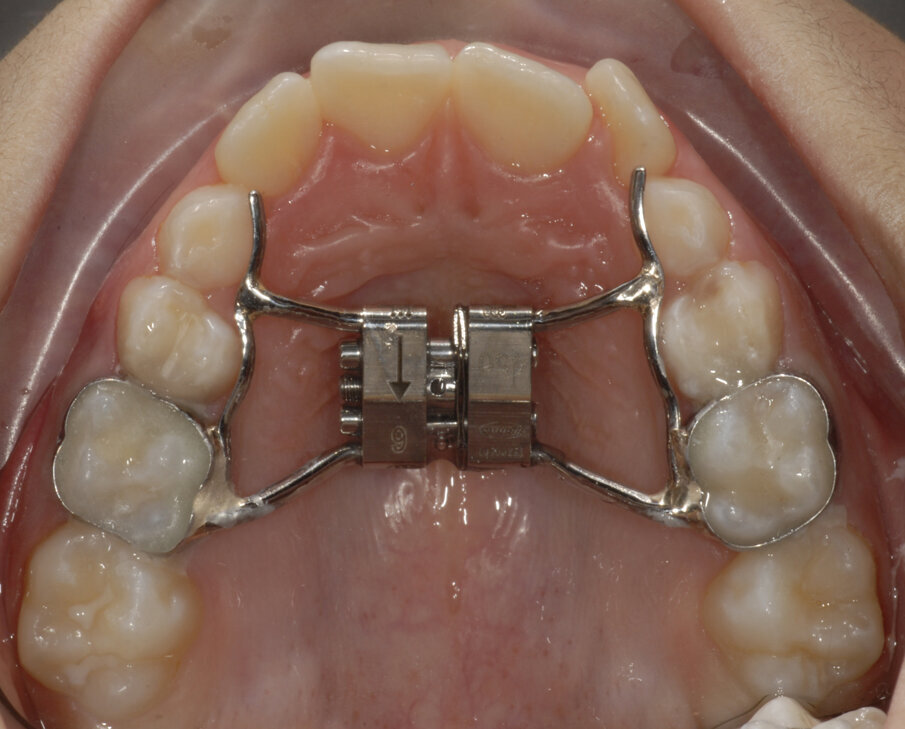

Dopo aver rilevato delle impronte con polivinilsilossano per realizzare un espansore del palato, si esegue l’espansione rapida del mascellare (Figg. 5, 6) superiore con il dispositivo cementato sui secondi molari decidui (5.5-6.5). Al termine dell’espansione, sono rilevate delle nuove impronte con polivinilsilossano per realizzare una barra palatale (Fig. 6) ancorata sui primi molari permanenti (1.6-2.6); viene eseguito un protocollo di estrazioni anticipate dei primi molari decidui e dei canini decidui (Figg. 7-9).

Fig. 5_Espansore rapido del palato ancorato su “E”.

Fig. 6_Termine dell’espansione.